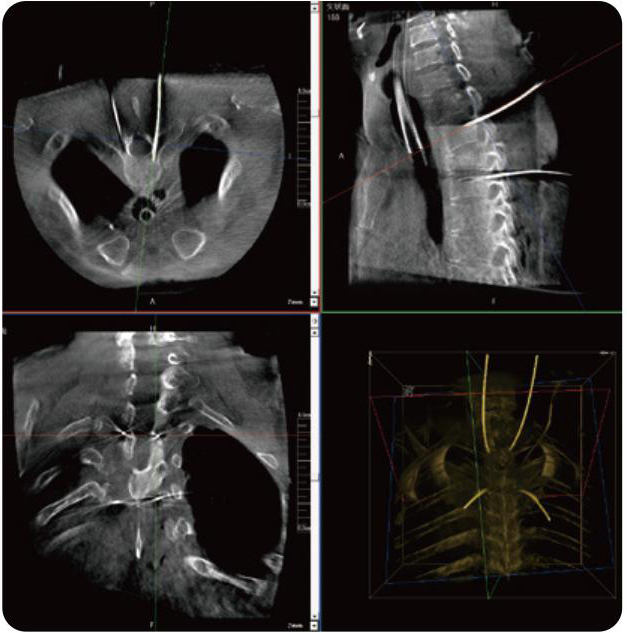

PL300B可應(yīng)用于多節(jié)段脊柱外科手術(shù),輔助醫(yī)生定位病灶部位,為脊柱外科手術(shù)(經(jīng)皮椎體成形術(shù)、椎弓根螺釘內(nèi)固定術(shù)等術(shù)式)提供術(shù)前手術(shù)流程規(guī)劃、入釘位置、角度可視化引導(dǎo),模擬仿真入釘輔助。

PL300B搭配普愛醫(yī)療自主研發(fā)生產(chǎn)的平板3D C形臂,借助一體化自適應(yīng)配準(zhǔn)( 軌跡配準(zhǔn))技術(shù),通過追蹤C(jī)形臂三維采集軌跡,自動(dòng)完成圖像坐標(biāo)建立和系統(tǒng)坐標(biāo)配準(zhǔn)。配準(zhǔn)精度更高,操作步驟少,系統(tǒng)運(yùn)作效率高。